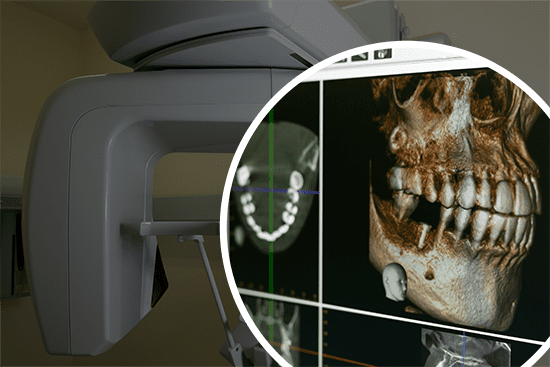

03 CT(3Dレントゲン)による三次元的な解析

マイクロスコープと同じく、CTも患部を正確に把握するための検査機器です。

通常、歯科治療ではレントゲンで検査することが多く、レントゲン検査でも大まかに口腔内の状況を把握することができます。しかし、歯科用CTを活用することでレントゲンでは発見できない小さな病変も可視化することができます。